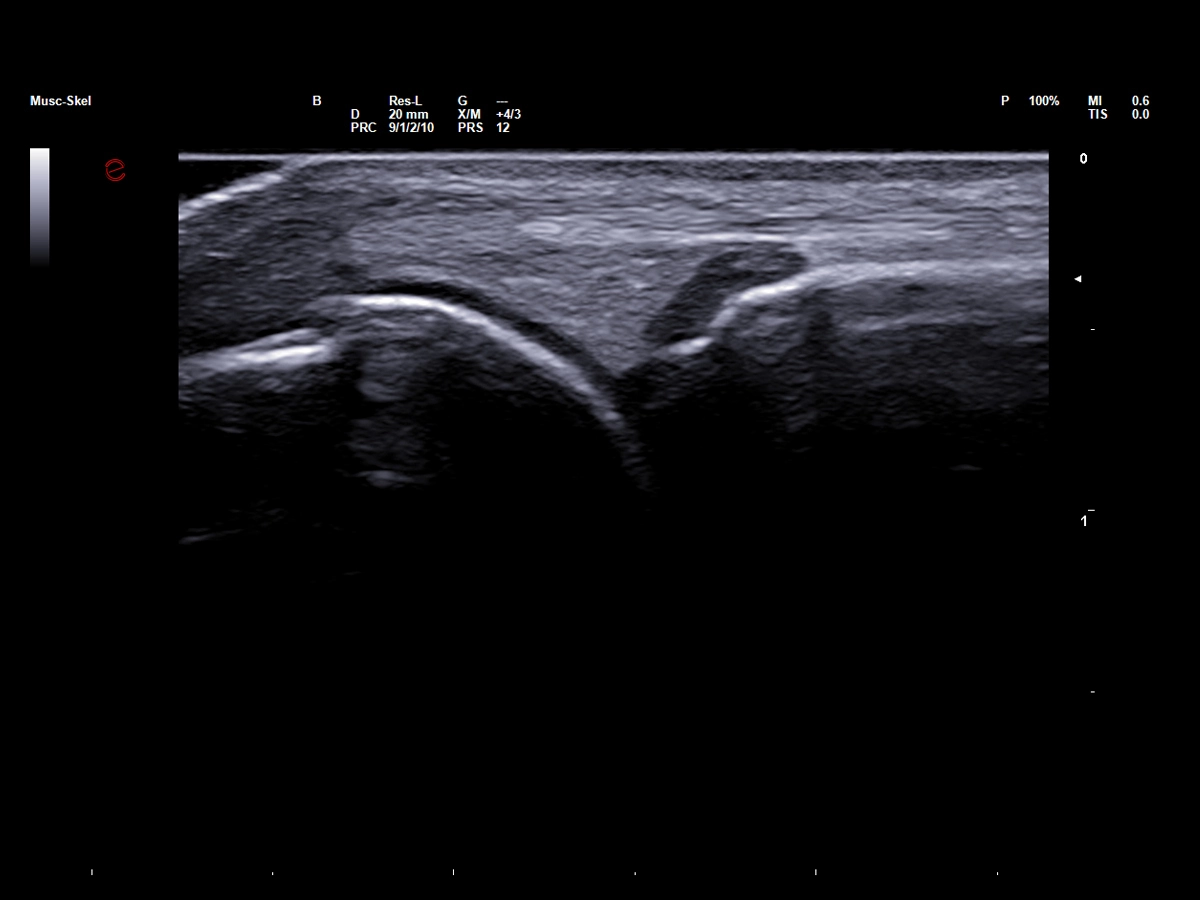

High-Frequency imaging for sport injury detection

Thanks to the advanced image quality of Esaote’s high-frequency probes, which operate at frequencies of up to 25 MHz, even micro-lesions can be clearly and precisely identified before they evolve into more serious injuries, thus empowering clinicians to stay one step ahead in injury prevention and management. The Very-High Frequency hockey stick probe, IHX 6-25, combines outstanding spatial resolution with advanced ergonomic design to facilitate needle access and perform accurate interventional gestures with millimetric precision.